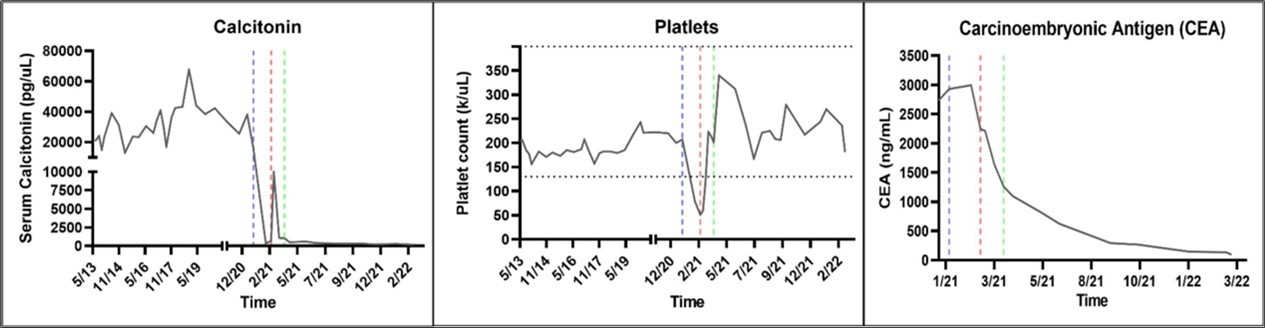

Figure 1.Biomarker Response. The patient’s calcitonin, platelet, and carcinoembryonic antigen levels were trended from May 2013 to March 2022. The dashed blue, red, and green lines indicate the start of Pralsetinib (400 mg PO QD), temporary hold of Pralsetinib due to grade 3 thrombocytopenia, and restarting of Pralsetinib at 200 mg PO QD respectively. Pralasetinib was effective in disease control as evidenced by significantly decreased calcitonin and CEA levels. When Pralsetinib held for thrombocytopenia, calcitonin level increased sharply. Pralsetinib at 200mg PO QD dose was adequate and effective in decreasing calcitonin and CEA levels without inducing thrombocytopenia.

The patient was re-referred to the Mays Cancer Center/UTHSA in November of 2020. The patient reported significant mobility issues and severe pain, rating a 3 on the Eastern Cooperative Oncology Group Performance Status (ECOG PS). Circulating tumor DNA (ctDNA) analysis (Guardant360) identified a RET 898-901Del and reported as a variant of unknown significance. Since the deletion was in the activation loop of RET kinase, the treating physician considered that the mutation was constitutively activating RET kinase. The patient was treated with Pralsetinib a small molecule inhibitor targeting the ATP-binding site of the RET kinase in December 2020 with a starting dose of 100mg per day with dose escalation every week to 400mg by mouth (PO) daily (QD). In January 2021 the patient noticed an improvement in quality of life (ECOG PS improved 2) with a significant decrease in serum calcitonin and CEA levels and decreased tumor size. The 400 mg PO QD dosing lead a decrease in platelet count to 51 K/mL in mid-February 2021. Pralsetinib was withheld for five weeks to allow for platelet recovery. In the interim the serum calcitonin level increased with disease progression. The patient was restarted at 200mg of Pralsetinib PO QD in March 2021 which was better tolerated with no further symptoms or signs of toxicity. The Pralsetinib treatment improved the patient’s mobility, pain, and over all quality of life, rating a 0 on the ECOG PS by September 2021.